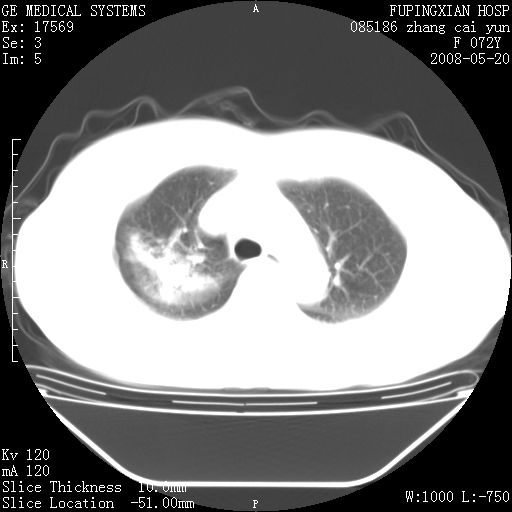

右上叶支气管走行自然,未见明显管壁增厚等征像,另左主支气管起始部可见异常腔道向左侧延展左肺动脉干后方,与左下叶支气管相通,为左下叶支气管变异?

有节段性阻塞性肺炎与不张,近段支气管狭窄,周围散在肿大淋巴结影,以周围型肺癌可能性大,建议纤支镜检查。

右肺上叶实变影,内见支气管充气征,右上叶支气管通畅,肺门区未见软组织密度影,抗炎治疗有效,考虑炎症,建议继续抗炎治疗复查。

考虑为:右肺上叶感染性病变。建议:1)继续抗炎治疗后复查。2)必要时行纤支镜检查。

右上肺实变,间内有支气管充气征,考虑炎症,建议抗炎后复查